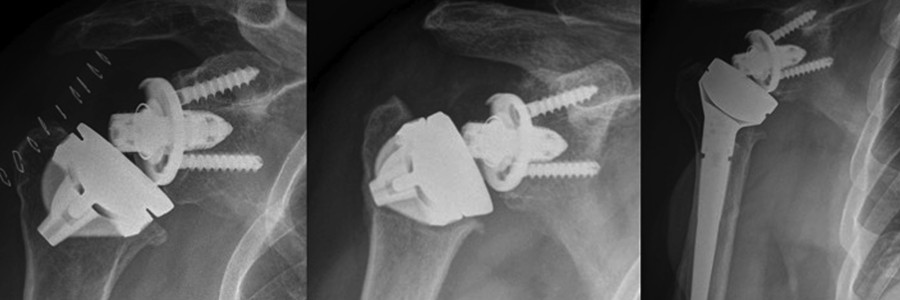

RAMA V ORTOPEDIJI

Letošnje srečanje bo namenjeno obravnavi patologije ramenskega sklepa. Slušateljem bomo med predavanji in pripravljenimi delavnicami skušali odgovoriti na pogosta vprašanja, ki se jim pojavljajo ob zdravljenju bolnikov z bolečino v ramenskem sklepu. Obravnavali bomo najpogostejše vzroke bolnikovih težav z ramo in slušateljem predstavili, kako najprimerneje postaviti diagnozo ter bolnika usmeriti v pravilno zdravljenje ob ugotovljenih težavah z ramenskim sklepom.